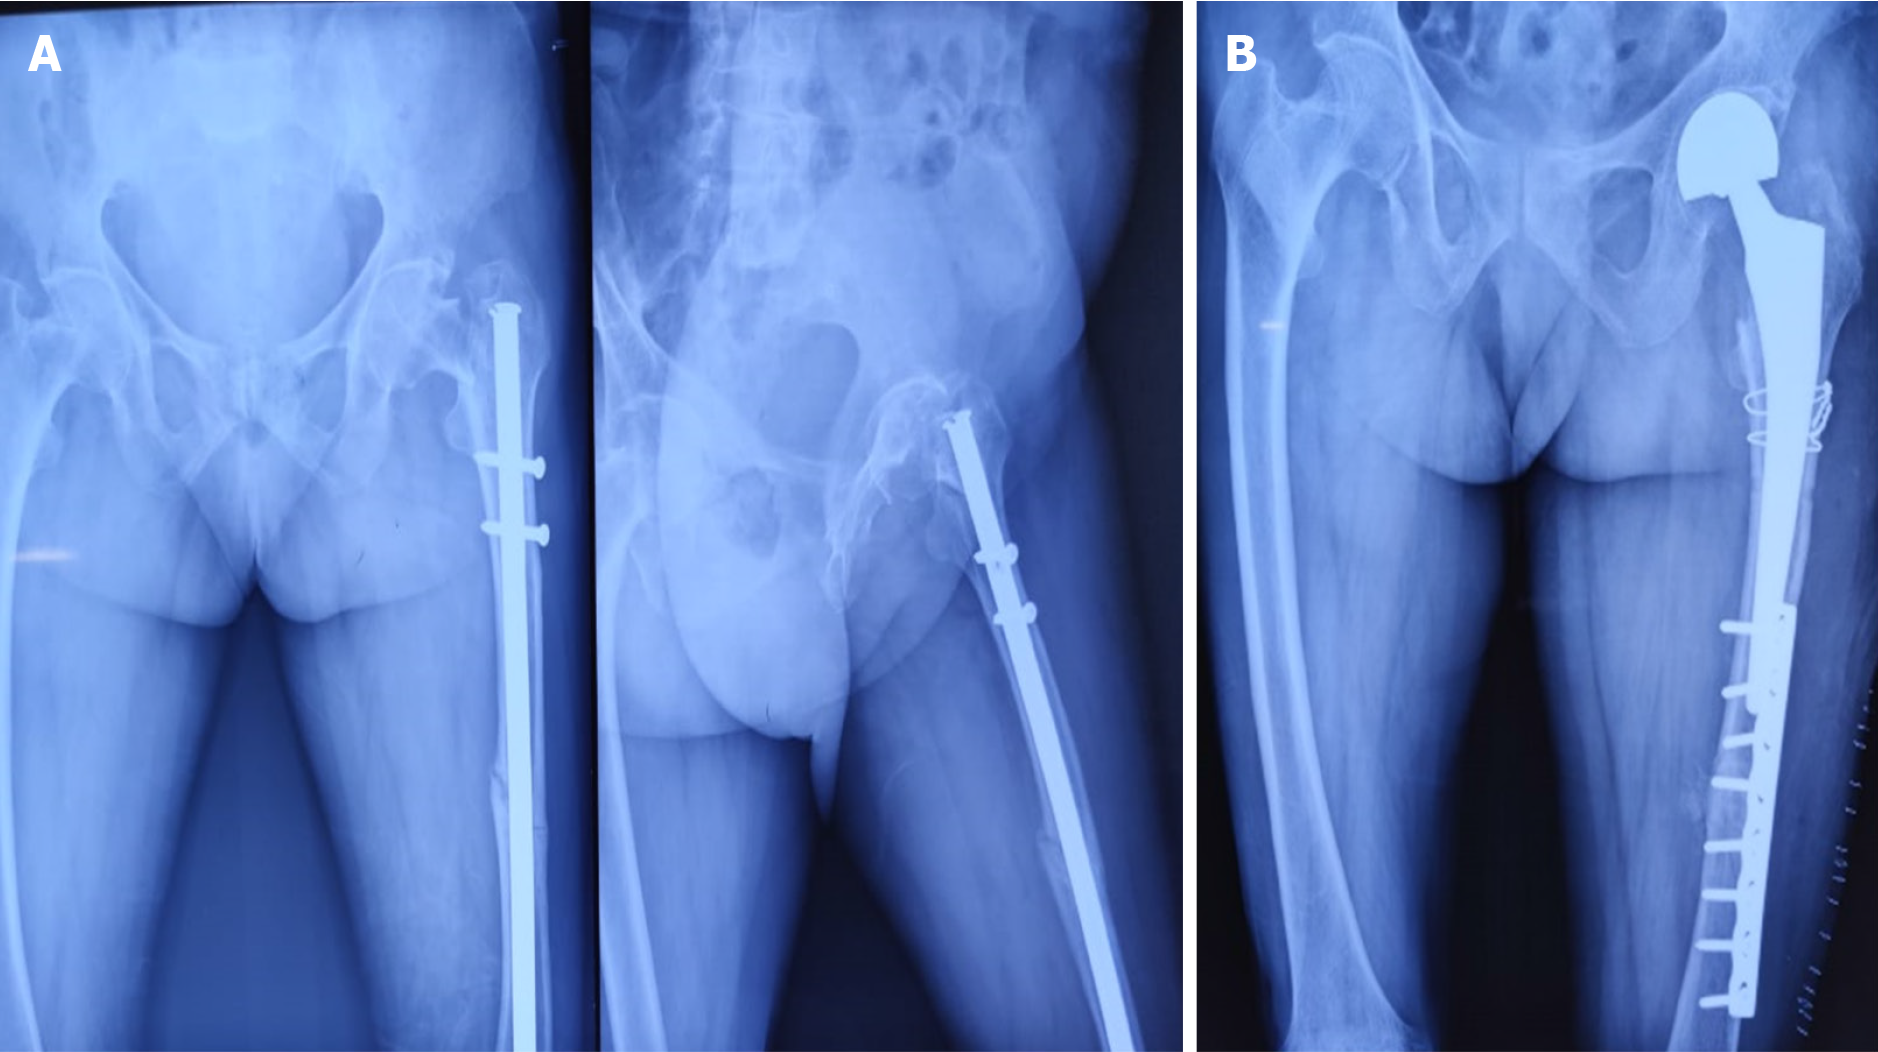

Fractures were diagnosed intraoperatively in 14 cases, immediately postoperatively in 1 case, and during follow-up (within 4 weeks) in 3 cases. The etiological breakdown included erroneous entry point (6 cases) as shown in Figure 3, inadvertent jig hammering (5 cases) as shown in Figure 4, misdirected nail manipulation (3 cases), hoop stress-related fractures (3 cases) as shown in Figure 5, and one case of unexplained origin. Intraoperative fractures were typically identified during final fluoroscopic checks, while postoperative fractures were detected on follow-up radiographs without intervening trauma Figure 6. The list of eitiologies contributing to iatrogenic fractures during femoral nailing is listed in Table 1.

| Unexplained origin | 1 | Immediate postoperative | Displaced | CCS (1) |

Among the 18 cases, 11 were undisplaced and 7 were displaced. Fixation methods included long proximal femoral nails (10 cases), cannulated cancellous screws (6 cases) as shown in Figure 6, bipolar hemiarthroplasty (1 case) as shown in Figure 7, and dual implant technique with limited contact dynamic compression plate (1 case) as shown in Figure 7. The “miss-the-nail” technique was employed in cases where the interlock nail remained in situ and removal was deemed risky due to potential displacement as shown in Figure 5 and Table 2.

Immediate postoperative imaging confirmed stable fixation in 15 cases and unstable fixation in 3 cases. Radiographic union of both shaft and neck fractures was achieved in 14 cases by 12 months. Four cases showed delayed union or incomplete healing at the neck site, including one requiring salvage hemiarthroplasty due to poor bone quality and late diagnosis. The average neck-shaft angle was 125° ± 10°, with no significant difference between fixation groups (P = 0.342) as shown in Table 3.